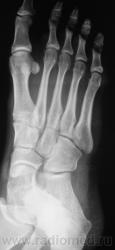

Травмы не было. Боли в переднем отделе стопы.

Но, юноша интенсивно занимается классической борьбой.

может в процессе борьбы и была получена трама? А может такая картина возникнуть как результат повышенной тренеровочной нагрузки, как перстройка костной ткани

Так а как иначе, чем лоозеровские зоны перестройки.

А. может "стресс-переломом" обругаем...

Оно то конечно можно, дабы поумерить пыл борца на какое то время...по пока, по сути, это не перелом.